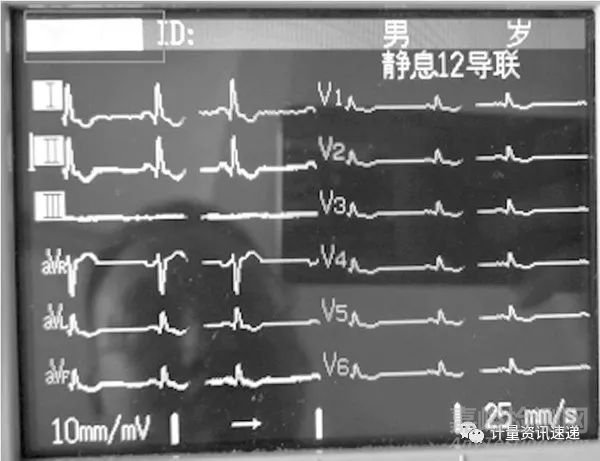

圖2 被檢心電圖機(jī)心率顯示界面

醫(yī)療機(jī)構(gòu)心內(nèi)科等重點(diǎn)科室多采用自動圖形分析能力較強(qiáng)的上?;蛉毡灸称髽I(yè)生產(chǎn)的數(shù)字心電圖機(jī)。但在實際檢測中按照圖1設(shè)置,該數(shù)字心電圖機(jī)心率顯示“***”,如圖3所示。

圖3 某品牌數(shù)字心電圖機(jī)心率顯示界面